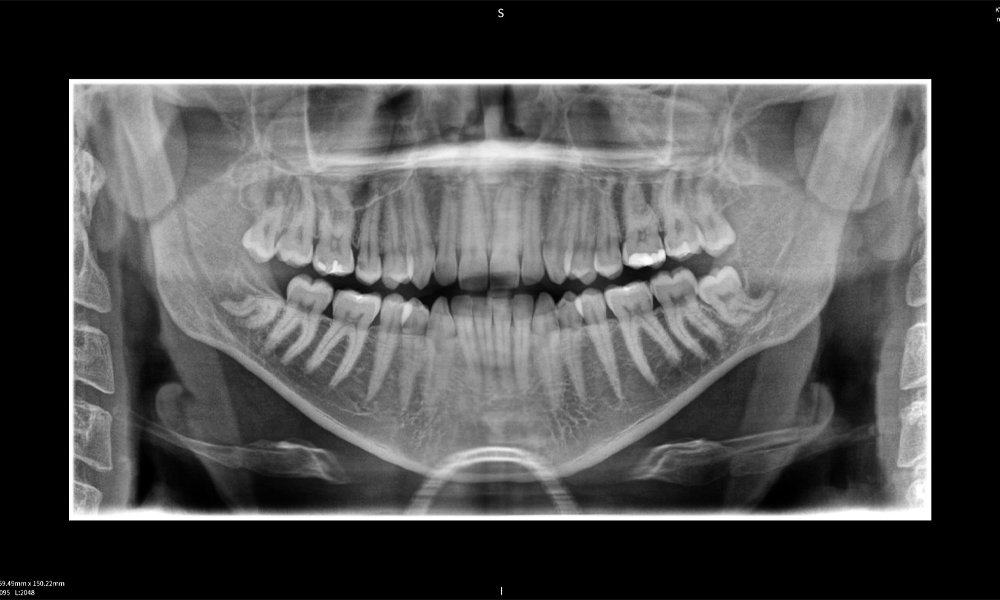

Below you will find a case from Dr. med. dent. Oliver A. Centrella, in which the CBCT images obtained with Seethrough Max provided crucial information on the complex anatomy and the critical relationship between the wisdom teeth and the inferior alveolar nerve. In this case, there is a indication for the surgical removal of the wisdom teeth.

Figure e: Imaging results of Seethrough Max, in front of a black background.

Figure e: The panoramic X-ray serves as an initial assessment tool, showing the general positioning of the teeth as well as any potential pathological changes. Notably, on the right side (tooth 48), the situation following a crown amputation performed by an external practitioner is visible. The two severely curved roots remain in close topographical proximity to the inferior alveolar nerve within the bone. This suggests a deliberate decision to avoid the increased risk of nerve injury during a complete extraction, and represents a clinically relevant finding. In summary, CBCT scans with Seethrough Max, provide crucial information about the complex anatomy and the critical relationship between the wisdom teeth and the inferior alveolar nerve. This detailed preoperative diagnostic imaging is essential for safe and successful surgical procedures in the mandibular region.